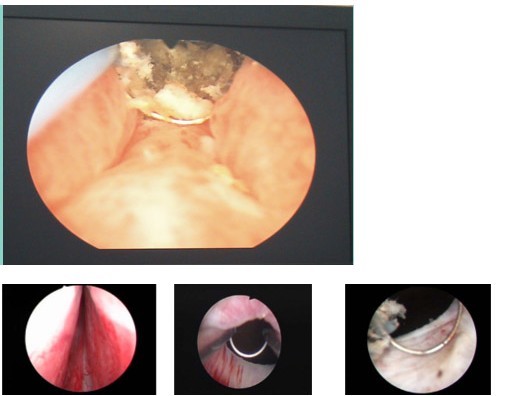

经皮肾镜下超声气压弹道混合动力碎石术:该项技术近年来发展较快,是肾脏及输尿管上段复杂结石治疗的一次革命,该技术避免患者腰部的大切口,仅需做一个肾穿刺造瘘,将肾镜引入肾内,直视下击碎结石,并将其吸出体外。其优点:创伤小,痛苦少,结石清除干净,具有可重复性。

2、前列腺气化电切术:该项技术已有20余年的治疗经验,它是通过尿道,将男性增生的前列腺组织在电切镜下切除,然后将切除的组织碎块冲出体外,从而,达到疏通尿道的目的。被形象地称为“人体下水管清道夫”。该技术的优点:创伤小、痛苦少,恢复快、并发症少。

3、输尿管镜下气压弹道碎石取石术:该技术是通过尿道,将镜体进入输尿管内达到结石位置在直视下,用气压弹道撞杆,直接撞击结石,达到碎石的目的。该方法,克服体外碎石对结石周围组织的损伤将外力直接作用于结石,隶属微创的手术范畴,深受广大患者欢迎。